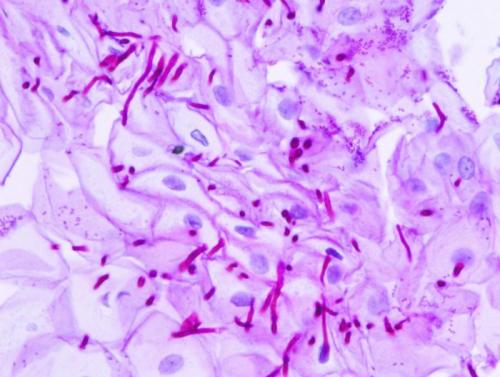

Нити мицелия иногда выявляются в мазках или соскобах с кожи, ногтей, половых органов.

Они могут появляться при различных инфекционных заболеваниях, вызванных грибками.

Если выявлены нити мицелия на коже, это признак грибкового её поражения.

У разных грибков мицелий выглядит по-разному.

После микроскопического исследования обычно доктор может определить, какой вид или хотя бы род грибов вызвал воспаление.

Мицелий обнаруживается чаще всего при дерматофитии.

Также может выявляться псевдомицелий.

Его вероятные причины – кандидоз и отрубевидный лишай.

Мицелий при трихофитии выглядит как сплетение тонких нитей.

Они представляют собой гифы.

Внутри них визуализируются перегородки.

Они называются септами.

Лучше всего мицелий выявляется при обработке раствором КОН с концентрацией от 10 до 30%.